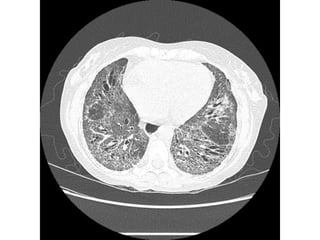

Pulmonary manifestations of

scleroderma

Bibasilar interstitial lung disease:

• Ground glass opacification.

• Reticular opacities & interlobular septal

thickening.

• Honey combing & traction bronchiectasis.

NO pleural effusion (DD with Rh & SLE).